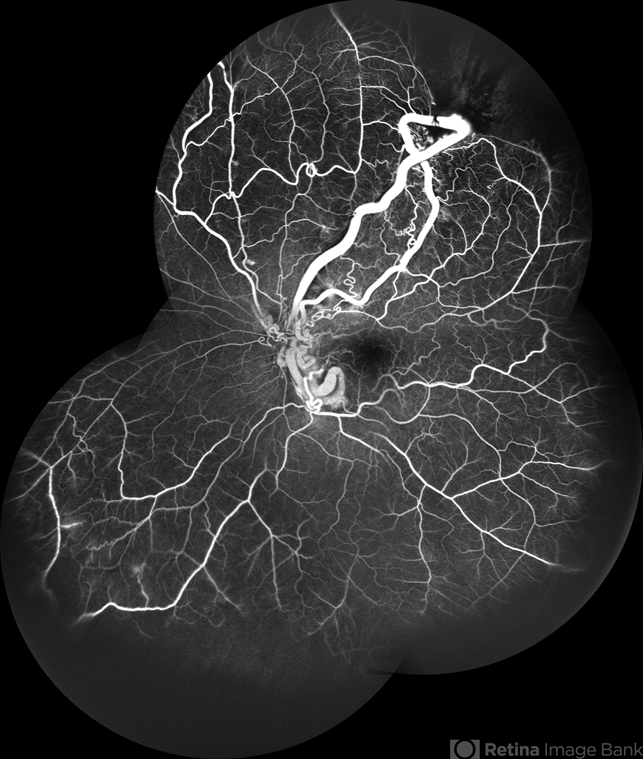

- racemose hemangioma, FFA in a case of Racemose angioma, arteriovenous malformation

- A case of 10 year old girl with defective vision in LE (6/60) who presented us with this condition.